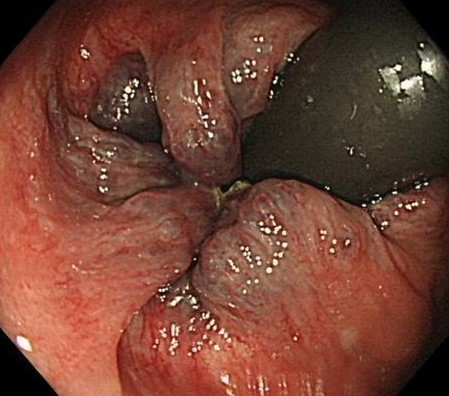

おしりの病気・・・痔(内痔核)

腫れがひどいと出血しやすくなります

ウォシュレットの普及により排便時の肛門環境は良くなり、以前より痔核は減りつつあります。しかし欧米人に比べ、日本人は痔になりやすく、切れて出血したり、便潜血陽性となることもあります。最近では、スマートフォンで画像を撮ってこられる方も多くなりました。痔は腫瘍ではありませんが、日常的な疾患として排便時の出血の原因となりやすい疾患です。多くの日本人が持っている痔が腫れて出血を認めたり、便に血が付くということがあります。

内痔核や外痔核・痔瘻などおしりの疾患も様々です。「痔を放っておいたら痛くて座れなくなってしまった」と受診された方で、痔瘻が悪化し広範囲の肛門周囲膿瘍となり緊急でドレナージというたまった膿を排出させる外科手術が必要な方もいます。